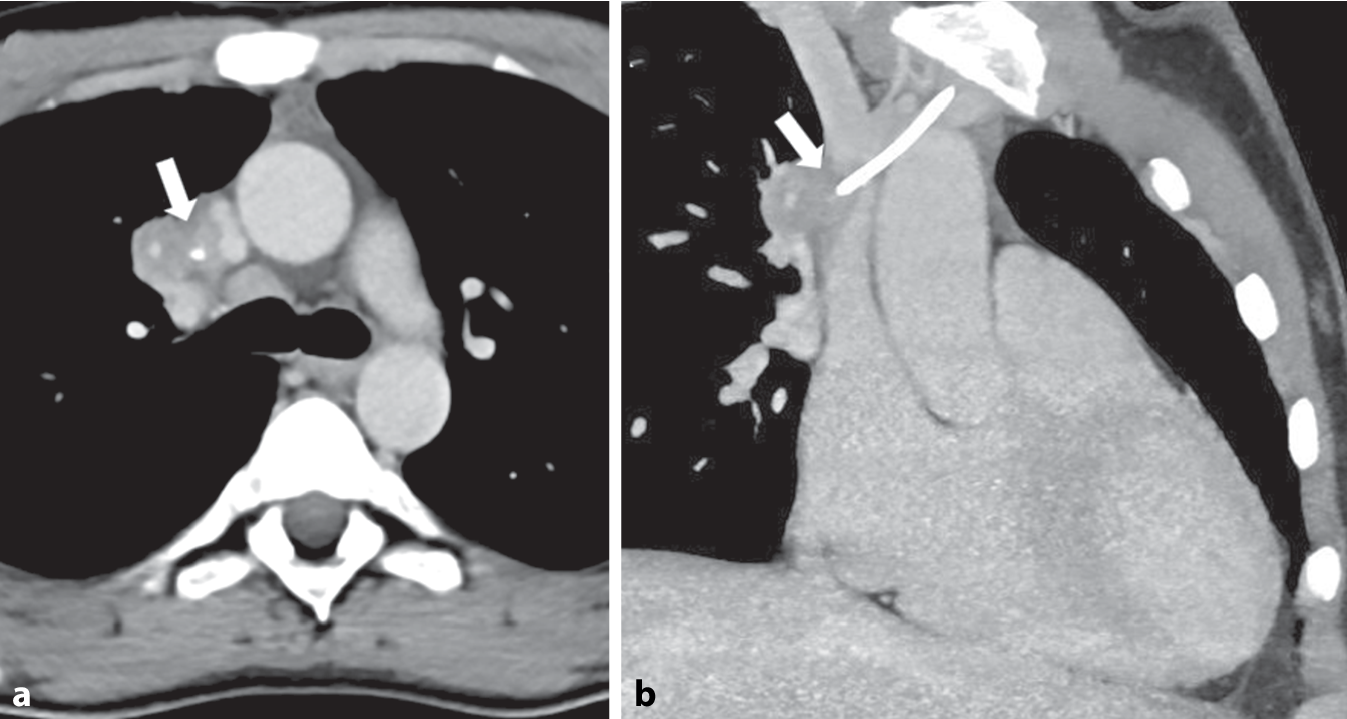

Zur weiteren Diagnostik wurde eine Durchleuchtungsuntersuchung des Portkatheters durchgeführt. In der initialen Leeraufnahme projizierte sich die Spitze des Portkatheters auf die Vena cava superior. Das Anspülen mit NaCl-Lösung war problemlos möglich, hierbei jedoch direkter Hustenreiz des Patienten auslösbar. In der anschließend angefertigten Durchleuchtungsserie unter Kontrastmittelapplikation zeigte sich eine Kontrastierung des an die Portspitze angrenzenden Bronchialsystems (Abb. 1a). Auch hierunter war ein deutlicher Hustenreiz auslösbar mit Nachweis von Kontrastmittel in der Trachea (Abb. 1b).

Abb. 1

Durchleuchtungsuntersuchung des Thorax mit Kontrastmittelgabe über den Portkatheter. Es zeigt sich zunächst eine Kontrastierung des Bronchialsystems (Pfeile) im rechten Oberlappen (a) und in der Folge auch der Trachea (Pfeile) bei Hustenreiz des Patienten (b)